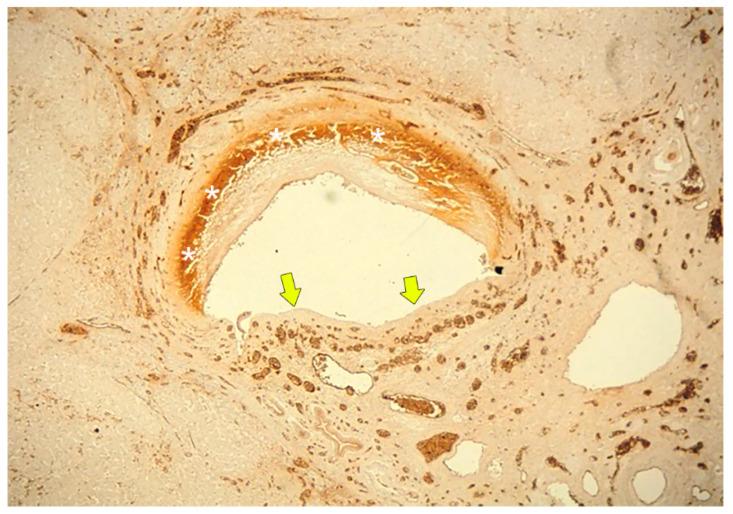

Bile duct necrosis (BDN) with biloma formation is a type of ischemic bile duct injury that is one of the serious complications associated with transarterial therapies, such as transcatheter chemoembolization therapy (TACE), and radioembolization for hepatocellular carcinoma (HCC) and hepatic arterial infusion chemotherapy (HAIC) for metastatic liver cancer from colorectal carcinoma. In terms of the occurrence of BDN and subsequent biloma formation, ischemic injury to the peribiliary vascular plexus (PBP), the supporting vessel of bile duct epithelium, is thought to be intimately associated. In this paper, we first describe the anatomy, blood supply, and function of the intrahepatic bile duct, and then illustrate the pathophysiology of BDN, and finally present the imaging findings of BDN. Under the process of BDN formation, ischemia of the PBP induces the disruption of the bile duct epithelial protection mechanism that causes coagulation and fibrinoid necrosis of the surrounding tissue by the detergent action of exuded bile acids, and eventually a biloma forms. Once BDN occurs, persistent tissue damage to the surrounding bile duct is induced by imbibed bile acids, and portal vein thrombosis may also be observed. On pre-contrast and contrast-enhanced computed tomography (CT), BDN shows similar findings to intrahepatic bile duct dilatation, and, therefore, it is sometimes misdiagnosed. Differentiation of imaging findings on CT and ultrasound (US)/magnetic resonance (MR) imaging/MR cholangiopancreatography (MRCP) is important for correct diagnosis of BDN.

伴有胆汁瘤形成的胆管坏死(BDN)是一种缺血性胆管损伤,是经动脉治疗相关的严重并发症之一,如经导管肝动脉化疗栓塞术(TACE)、肝细胞癌(HCC)的放射性栓塞以及结直肠癌肝转移的肝动脉灌注化疗(HAIC)。就BDN的发生及随后胆汁瘤的形成而言,胆管周围血管丛(PBP)(胆管上皮的支持血管)的缺血性损伤被认为与之密切相关。在本文中,我们首先描述肝内胆管的解剖结构、血液供应和功能,然后阐述BDN的病理生理学,最后介绍BDN的影像学表现。在BDN形成过程中,PBP的缺血会导致胆管上皮保护机制的破坏,渗出的胆汁酸通过去污剂作用导致周围组织发生凝固性坏死和纤维蛋白样坏死,最终形成胆汁瘤。一旦发生BDN,吸收的胆汁酸会导致周围胆管持续的组织损伤,还可能观察到门静脉血栓形成。在平扫及增强计算机断层扫描(CT)上,BDN表现与肝内胆管扩张相似,因此有时会被误诊。CT及超声(US)/磁共振(MR)成像/磁共振胰胆管造影(MRCP)上影像学表现的鉴别对于BDN的正确诊断很重要。